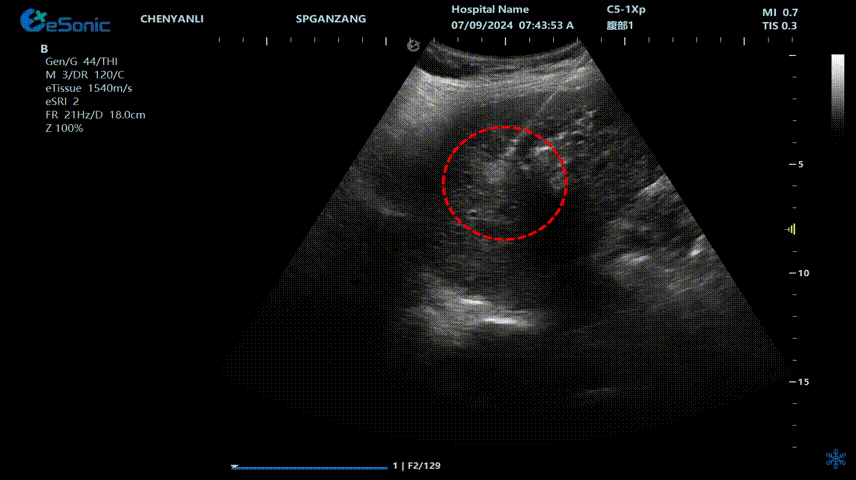

肝癌射频消融动态视频

红圈为病灶位置

肝癌射频消融:全麻下彩超探头引导射频针分别植入肝右叶两个稍高回声结节,固定消融,至结节全部为强回声覆盖,覆盖良好,缓缓灼烧针道后退针。